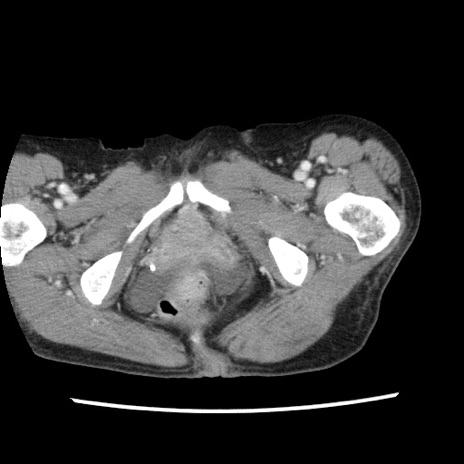

症例1(横断像)

【症例】80歳代女性

【主訴】腹痛

【現病歴】8時間前から腹痛あり来院。

【既往歴】糖尿病、脂質異常症、子宮体癌にて子宮全摘術

【身体所見】意識清明・会話良好だが腹痛で苦悶様、全腹部にわたって反跳痛と圧痛あり

【データ】WBC 13600、CRP 0.14、LDH 224、CK 90